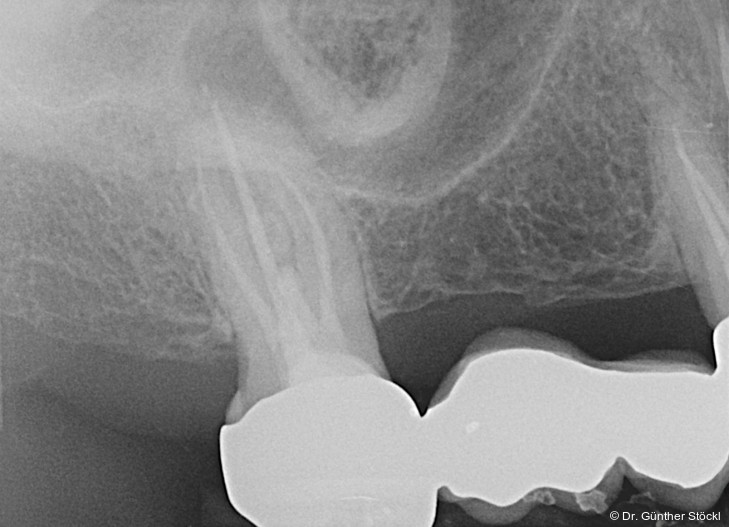

Foto: Dr. Günther Stöckl